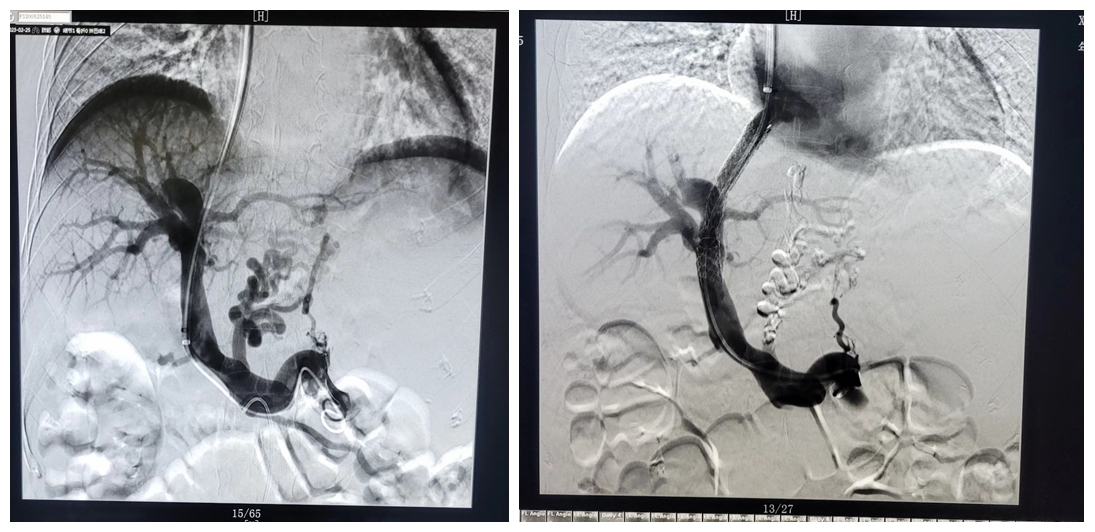

近日,我院成功开展首例经颈静脉门体分流术(TIPS)+胃冠状静脉栓塞术(GCVE)。

通过与患者及家属的反复沟通,详细告知该治疗方案的优缺点及替代治疗方案后,患者及家属同意该治疗方案。手术由普外二科和医学影像科共同准备,经过前期充分的准备工作后,由中科大一附院成德雷主任带领影像科介入亚专科小组张涛、汪骏2名医师顺利完成手术。目前患者恢复良好,现已出院休养。